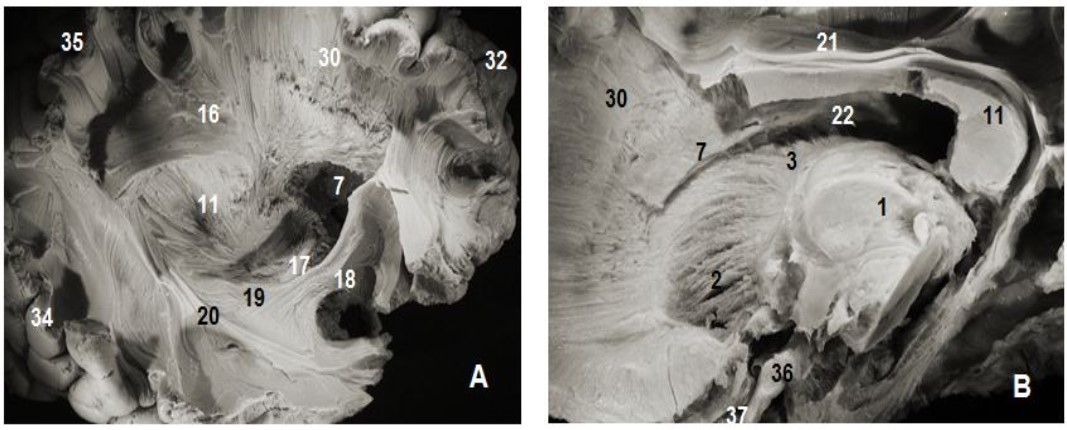

Thalamic radiations or thalamocortical pathways are reciprocal myelinated nerve fibers, arranged in a fanning pattern, grouped into tracts or fasciculi; and connecting the thalamus to the cerebral cortex (Figure 2, Figure 3, Figure 4). They are the most medial fibers of the internal capsule and consist of anterior (thalamofrontal), superior (thalamo-fronto-parietal or thalamoparietal), posterior (thalamooccipital) and inferior (thalamotemporal) thalamic fasciculi.

Figure 2.Subependymal stratum: (A) lateral view of right hemisphere and (B) medial view of left hemisphere. 1.Thalamus, 2. Anterior thalamic radiation, 7. Subependymal substratum, 4. Ependymal membrane, 6. Lateral ventricle, 11. Splenium of corpus callosum, 21. Cingulum, 30. Corona radiata, 32. Parietal pole, 33. Frontal pole, 35. Occipital pole, 36 tract optic

Figure 3.Thalamic radiations: (A) lateral view and (B) medial view. 1. Thalamus, 2. Anterior thalamic radiations, 3. Superior thalamic radiations, 4. Posterior thalamic radiations, 5. Inferior thalamic radiations, 6. Ventricular landmark, 10. Tapetum of corpus callosum, 11. Splenium of corpus callosum, 22. Ependymal membrane, 23 .Pons , 24. Mesencephalon, 17. Optic tract, 18. Uncinate fasciculus, 31. Occipital pole, 36. Cerebellum, 37.Frontal pole.

Anterior and superior thalamocortical pathways course obliquely and connect anterior, mediodorsal, lateral ventral anterior, lateral dorsal and lateral posterior thalamic nuclei to the cerebral cortex. They exposed after the removal of the head and body of the corpus callosum were . A coronal view of the thalamus confirms the course of these fibers to the thalamus. The sub-ependymal stratum and gray matter are medial to the thalamic radiations (Figure 1). The successive excision of the insular cortex, claustrum, fibers of the extreme capsule, the putamen and globus pallidus and pyramidal tract exposed other components lateral to the internal capsule (Figure 1, Figure 4). Fibers of the extreme and external capsules and of the lenticular nucleus (putamen and globus pallidus) formed an inferior relationship with the stem of the uncinate and the inferior occipitofrontal fasciculi. A coronal section through the cerebral hemisphere and the thalamus completed the study of thalamic radiations. The optic radiations and the ventral amygdaloid tract which loop through the anterior perforated substance and the lateral expansion of the anterior commissure sheathed by the Gratiolet canal, which were not include intentionally in our illustrations, were further away. Gratiolet optic radiations connect the thalamus to the geniculate body and the posterior nucleus of the occipital cortex. These thalamic radiations line up the lateral ventricle.

The thalamus sends fibers in all directions. Anteriorly, the thalamo-fronto-parietal fasciculus connects the anterior and medial lateral nuclei to the cortex of the frontal pole. Superiorly, the thalamo-parietal bundle unites the anterior and intermediate latero-ventral nuclei to the posterior frontal and prefrontal cortex, and the lateral postero-ventral nuclei to the sensory associative parietal cortex. Posteriorly, the thalamo-occipital fasciculus connects the lateral geniculate body and the posterior nucleus to the occipital cortex. Posterior and superiorly, the thalamo-parietal fasciculus connects the dorso-lateral nuclei to the posterior associative cortex.

Posterior and inferiorly, the thalamotemporal fasciculus unites the posterior nucleus and the lateral geniculate body to the temporal cortex.

The internal capsule was exposed after the excision of the putamen and globus pallidus which were perfectly identifiable. The abscission of the outermost fibers of the internal capsule situated approximately 26 mm from the cerebral cortex and the head of the caudate nucleus exposed thalamic radiations (Figure 3).